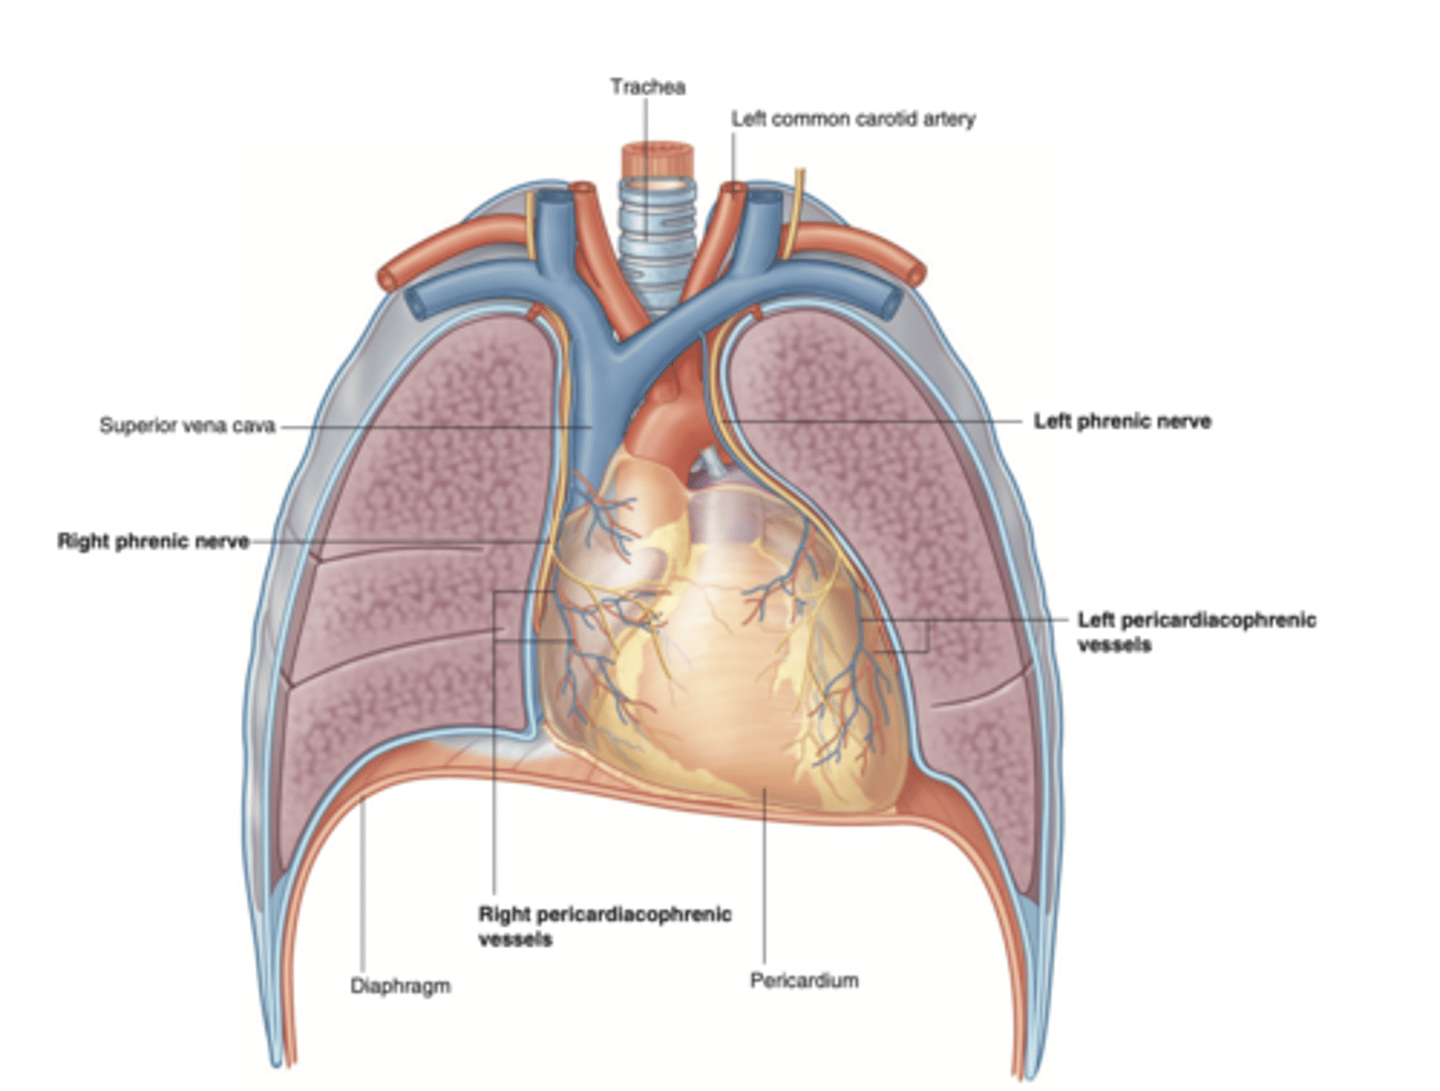

Where is the heart located?

The heart is located in the middle mediastinum, surrounded by the pericardium.

PERICARDIUM : FIBROUS SAC SURROUNDING THE HEART AND THE ROOT OF THE GREAT VESSELS